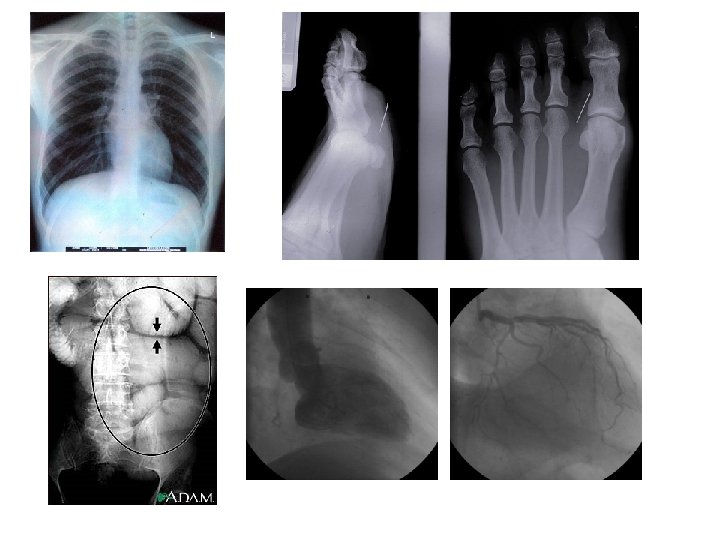

DIFERENTES USOS DE LOS RAYOS X • Visualización del esqueleto • Radiografía de pecho – Identifica neumonía, cáncer de pulmón, edemas pulmonares • Radiografía abdominal – Identifica bloqueos del intestino, perforaciones, piedras en la vesícula o riñones • Angiografía • Mamografía

USO DE CONTRASTES • En los rayos X normales (utilizados especialmente para visualizar huesos) no se observan los tejidos blandos. • Para poder visualizar órganos o vasos sanguíneos se debe utilizar un medio de contraste. • Los medios de contraste son líquidos que absorben rayos X mejor que los tejidos que los rodean.

USO DE RAYOS X CONTRASTE • Para visualizar órganos del tracto digestivo y endocrino: – El paciente toma un liquido que es un medio de contraste, generalmente un complejo de bario • Para visualizar elementos del sistema circulatorio (angiografía): – Se le inyecta al paciente el medio de contraste en la circulación

USO DE RAYOS X CONTRASTE • El medio de contraste va a ser mas claro que los tejidos de alrededor, por lo que lo podemos visualizar en el negativo, y podemos observar el paso del contraste por el sistema. • Se utiliza en conjunto con un fluoroscopio. Los rayos X pasan a través del cuerpo hacia una pantalla fluorescente, creando una imagen de rayos X en movimiento (según el movimiento del medio de contraste en el sistema)